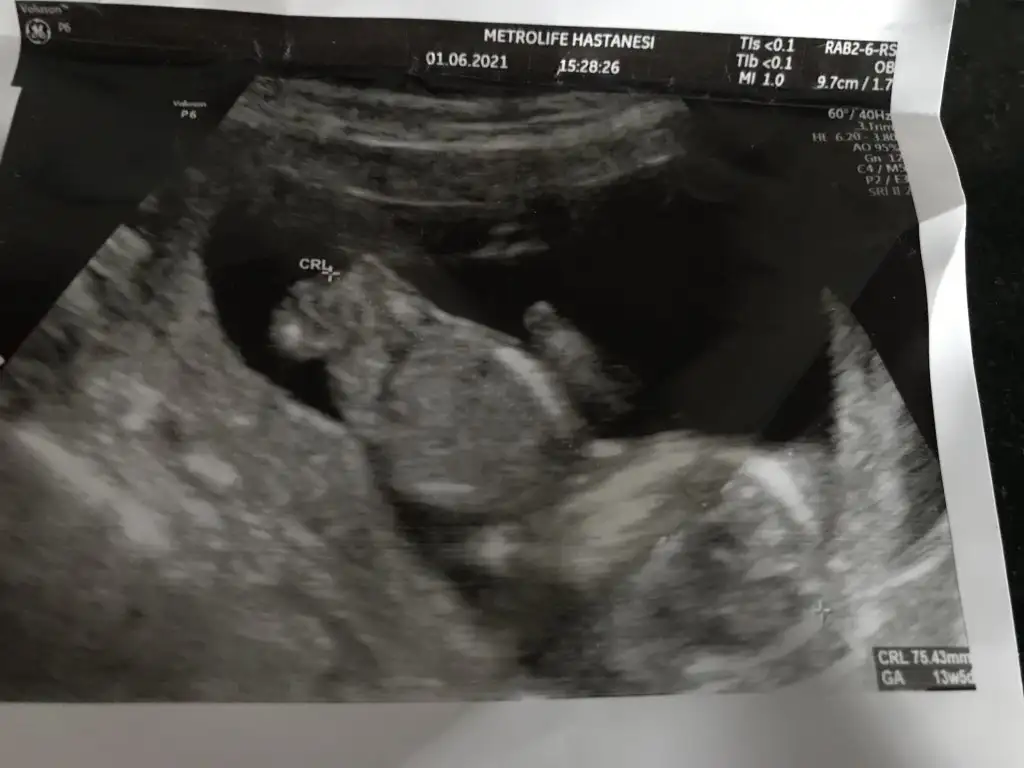

Az önce dr dan geldim. Bana kız dedi ya 17hafta olduk. 12.haftada da kiz demisti. Tum belirtilerim erkekti amaErkek görünüyor![]()

Kız gibi sanki daha önceki karanlık USG emin olmamıştımBen bugün gene kontroldeydimIkra meyra her seferin farklı tahminde bulunuyor ama bugün met ve emin söyledi. Bakalım sen ne diyeceksin? Bemce poposu dönük ama öyle bişey demedi.

Evet bu sefer de kız dedi kesin konuştu ama ben 20. Hafta detaylıyı beklecepim emin olmak için. Teşekkür eserimKız gibi sanki daha önceki karanlık USG emin olmamıştım

En iyi 11 12 13 haftalar olmalı şimdilik kız yönünde ama yanıltabilirIkra meyra bana da yorum yapar mısın cinsiyet için